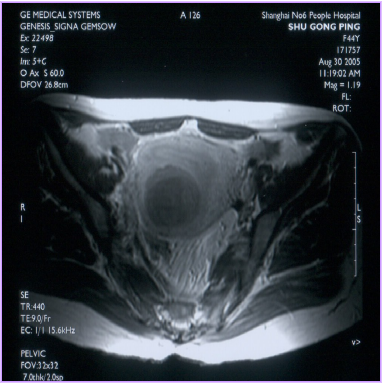

治療后壞死的子宮肌瘤不會(huì)消失,而是會(huì)發(fā)生纖維化,緩慢縮小,但對(duì)人體已經(jīng)沒(méi)有危害了。最近,由于磁共振增強(qiáng)掃描(圖1,2)和超聲造影檢查技術(shù)(圖3,4)的應(yīng)用,使治療效果的評(píng)價(jià)更加客觀和明確。

圖1 治療前MRI增強(qiáng)掃描